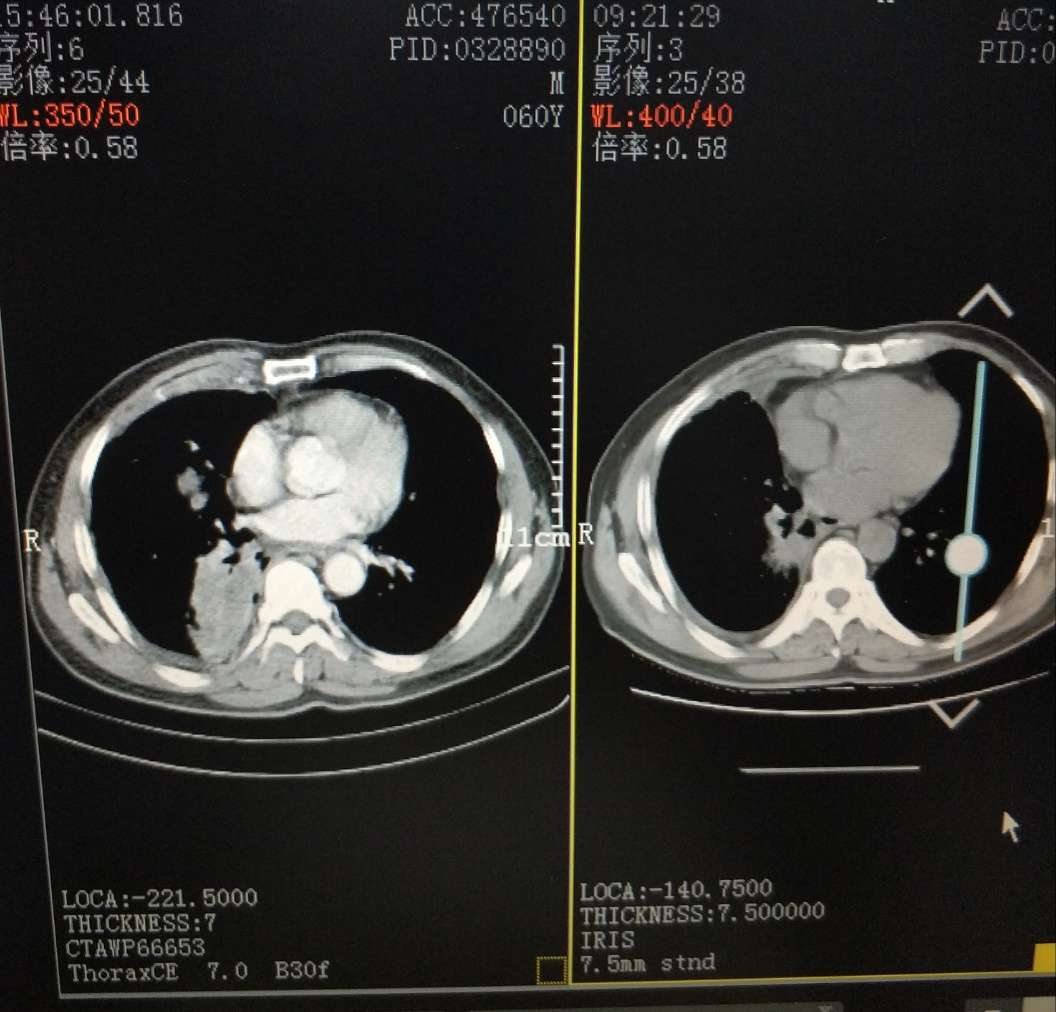

晚上好,我爸爸胸水控制不住周一转到浙二滨江呼吸科就诊,19突变易瑞沙吃2个月时间,昨天CT做出来医生说相比较上次9月18日肿瘤还大了而且有新的,医生建议易瑞沙可能耐药才2个月时间,易瑞沙没效果,前天还咳血了15ml鲜红色,今天中午又咳血了一口,医生建议化疗药卡铂+培美曲塞,或者做其他有靶向药的全基因检测,这两天开始吃善存维生素片,+白蛋白偏低自费打了白蛋白针和香菇多糖,我这两天压力很大,不知道该怎么办好,希望能够得到您的一些建议,谢谢,谢谢